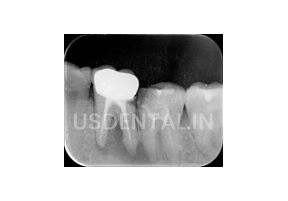

A young male patient visited US Dental clinic with pain in the lower left side of the jaw. We did a clinical and radiographic examination and we found that the lower 1st molar on the left side was already root canal treated and the patient had infection around that tooth. Patient also informed us that he is getting to swell on the gums often and that the tooth was treated with root canal treatment twice. After examination with 3D x-ray, we found that bone resorption was there on the buccal side due to the presence of infection.

Here is the x-ray of pre pre-procedure